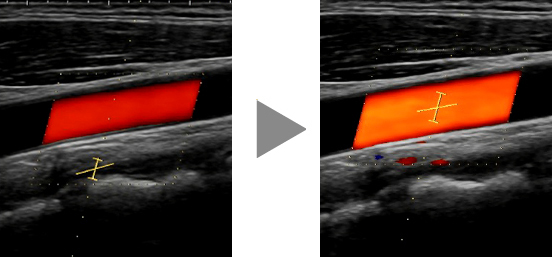

Los ajustes como la posición de la región de interés de color y el cursor se pueden configurar con un solo clic en el examen Doppler de un vaso. También se admiten transductores convexos. Además, el IMT automático puede medir automáticamente el grosor íntima-media (Intima-Media Thickness, IMT).

Vascular puede ajustar los parámetros como la posición de la región de interés de color y la posición/tamaño/ángulo de la puerta de muestra con un solo clic de un botón en un examen Doppler de un vaso.

Debido a que esta función también está disponible en la pantalla del trapezoide, se puede esperar que acorte el tiempo de examen no solo para una arteria carótida, sino también para un vaso de la extremidad inferior.